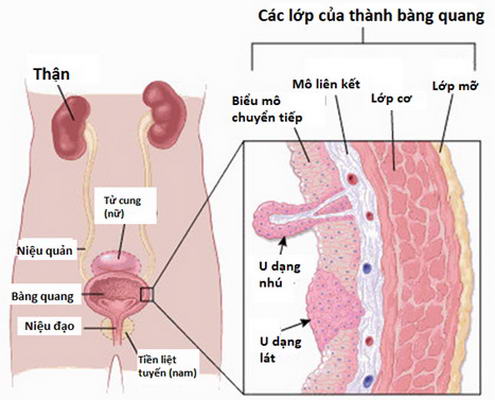

Ung thư bàng quang là gì?

Bàng quang là cơ quan hình quả bóng nằm trong vùng xương chậu, chứa nước tiểu. Ung thư bàng quang là loại ung thư xuất phát từ các tế bào lót bên trong bàng quang, có thể xảy ra ở mọi lứa tuổi nhưng thường gặp nhất ở người lớn tuổi.

Hầu hết ung thư bàng quang được chẩn đoán ở giai đoạn sớm, khi cơ hội điều trị khỏi bệnh rất cao. Tuy nhiên, ngay cả ở giai đoạn sớm, bệnh vẫn có thể tái phát. Do đó, sau điều trị, bệnh nhân ung thư bàng quang thường được theo dõi trong nhiều năm để phát hiện tái phát kịp thời. Phẫu thuật cắt bỏ tuyến tiền liệt bằng laser